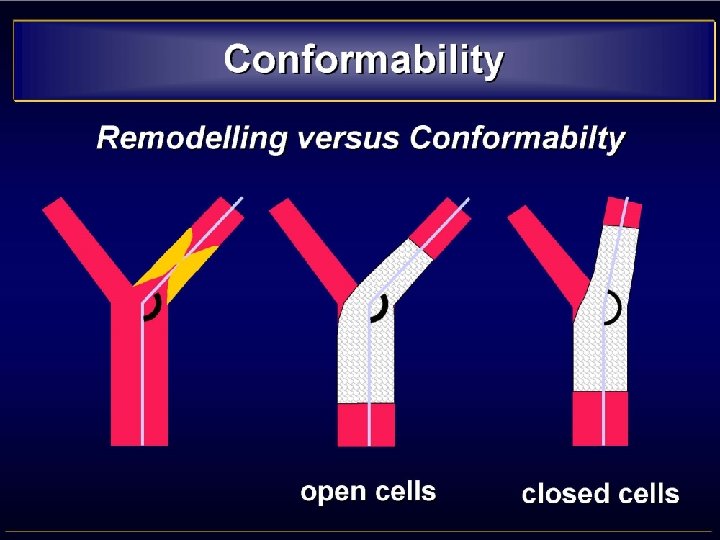

TORTUOUS CAROTID • CONSIDERATIONS - Tend to be straightened out by stents - Resulting in kinking above the stent -A flexible device is mandatory • STENTS REQUIREMENTS - Flexibility - Trackability - Conformability • CHOICE Open-cell design follow the curves better